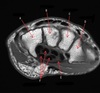

7

Q

What is letter A?

A

SUBSCAPULARIS MUSCLE

How well did you know this?

8

What is letter B?

HEAD OF HUMERUS

1

Not at all

2

3

4

5

Perfectly

9

What is letter C?

INFRASPINATUS MUSCLE

10

What is letter D?

GLENOID